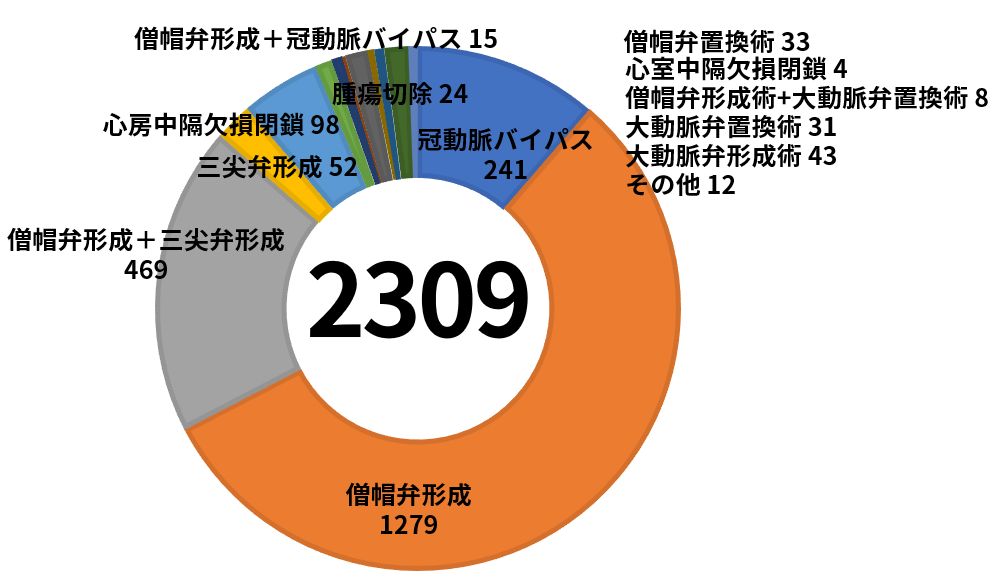

私たちは手術成績を公開し、納得していただける先端治療を提供できるように尽力します。

手術支援ロボット“ダビンチ(da Vinci Surgical System)”を用いた手術が行われるようになり、これまでよりも心臓疾患手術の術式の幅が広がったため、多くの症例へのアプローチが可能になりました。当院では2022年8月に1000例の手術実績があります。心臓疾患をお持ちの患者様へ迅速に手術へと踏み切ることが可能になったことで、完治へと導いた件数が飛躍的に増加しました。診療実績とその経過が手術の精度を実証していることでしょう。

心臓疾患手術にオールマイティに汎用した

手術を実践

患者様自身の弁やその周囲の形を整え、弁の機能を回復させる手術です。

弁置換術は患者さんの悪くなった弁を取り除き、生体弁もしくは機械弁に取り換える手術です。